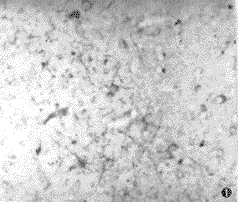

摘要 目的 探讨异常PrP沉积形式与Creutzfeldt-Jakob病(CJD)、Gerstmann-Straussler综合征(GSS)临床与病理关系。方法 经病理检查确诊的7例CJD,1例GSS脑切片进行朊蛋白PrP免疫组化染色和实验动物传递。结果 (1) 7例CJD均呈现突触型阳性,而GSS则呈现斑块型阳性;(2)突触型阳性者,病程短,平均12.3个月,斑块型阳性者病程60个月;(3)7例突触型均有痴呆,6例有肌阵挛,小脑症状不明显,斑块型则与其相反;(4)突触型中4例进行动物传递均获成功,斑块型则否;(5) 突触型PrP沉积多位于大脑灰质,斑块型多在小脑分子层。结论 应用水解高压灭菌法,以PrP抗血清为第一抗体的免疫组化方法,可以准确判定异常PrP沉积的两种类型,二者神经症状、病程长短、脑电图改变以及动物传递结果等均不相同。